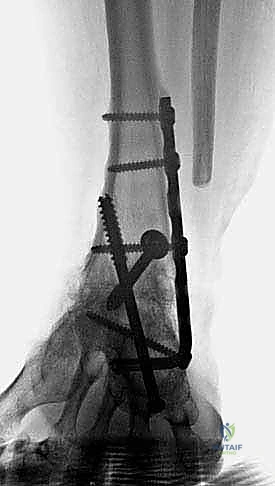

Follow-up (3 years)

The second screw, from the posterior tibia to the center of the talar head, lags the talar head to the prepared anterior distal tibial surface ( TECH FIG 11H ). An AP view of the foot confirms that the guide pin is in the center of the talar head.)())((()) ). An AP view of the foot confirms that the guide pin is in the center of the talar head.

Patient is ambulating comfortably without an assistive device; only a slight limp is appreciable.

She was issued a brace with a small lift but does not routinely wear it.

She is far more functional than preoperatively.

Obtain fluoroscopic confirmation of the construct in the AP, mortise, and lateral planes.

Radiographs demonstrate solid ankle and hindfoot fusion with near-physiologic alignment ( TECH FIG 12 ).

TECH FIG 12 • Final follow-up radiographs 3 years after procedure. A. AP view. B. Lateral view. A B